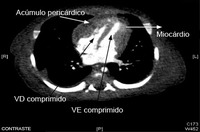

Tomografia computadorizada (TC) do tórax em um bebê com pericardite purulenta, mostrando uma coleção pericárdica com compressão dos ventrículos esquerdo (VE) e direito (VD)

Karuppaswamy V, Shauq A, Alphonso N. BMJ Case Reports 2009; doi:10.1136/bcr.2007.136564